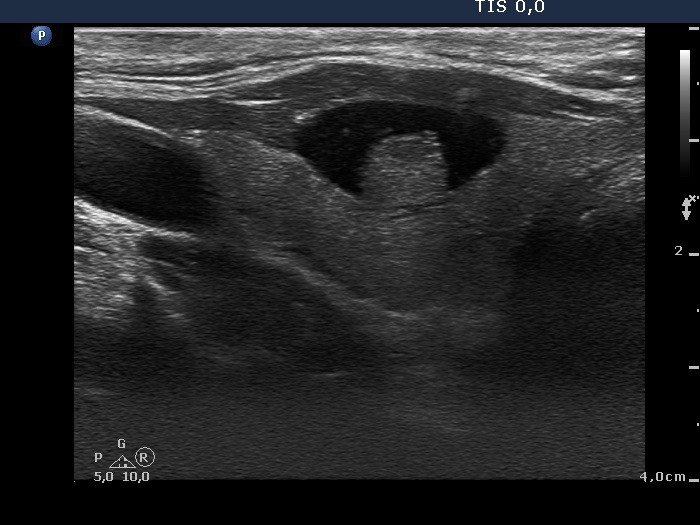

Benign cystic nodule (cytology and wash-out) - case 2177

Transverse scan

According to the EU-TIRADS, this lesion cannot be regarded as a purely cystic nodule due to the presence of wall-thickening (yellow arrows). The EU-TIRADS defines this lesion as an EU-TIRADS 3 nodule.